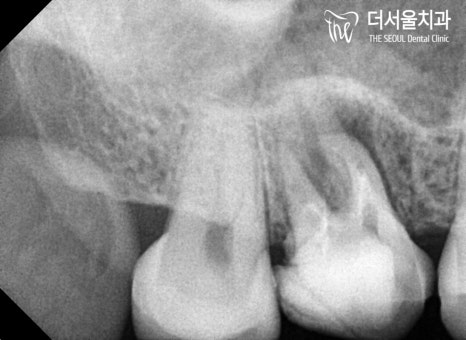

이미 채워져 있던 근관 내부를

깨끗이 청소한 뒤에

근관 세척 및 충전 과정을 거쳤습니다.

미처 제거되지 않은 곳이 있는지

긴장의 끈을 놓지 않고 여러 번 확인했습니다^^

드디어 리엔도 과정이 끝났는데요.